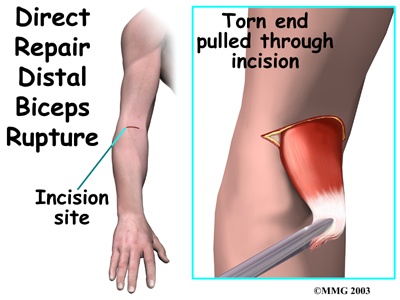

Direct repair surgery is commonly done soon after the rupture. Doing a direct repair soon after the injury lessens the risk of tendon retraction.

In a direct repair, the surgeon begins by making a small incision across the arm, just above the elbow. Forceps are inserted up into this incision to grasp the free end of the ruptured biceps tendon. The surgeon pulls on the forceps to slide the tendon through the incision.

Attention is given to the . A scalpel is used to slice off the damaged and degenerated end. Sutures are then crisscrossed through the bottom inch of the distal biceps tendon.